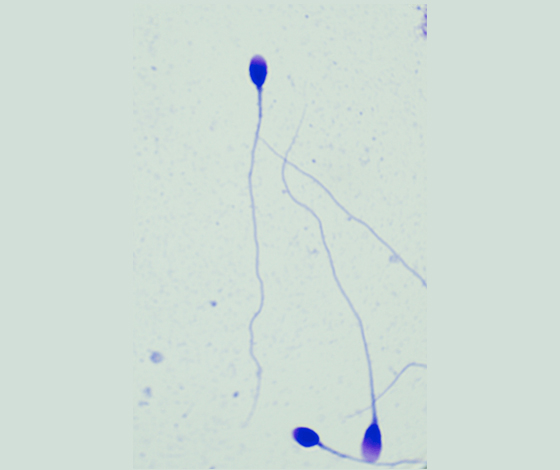

染色結(jié)果示意圖:

采用世界衛(wèi)生組織(WHO)推薦方法配制的精子形態(tài)快速染色液,對(duì)精子涂片進(jìn)行染色,精子頂體區(qū)、體部、尾部呈現(xiàn)不同的著色,觀(guān)察正常精子的形態(tài)百分比。